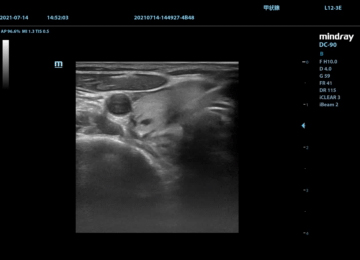

甲状腺结节的细针穿刺

近年来,甲状腺超声检查成为了人们每年体检的普查项目,随之甲状腺结节检出率显著上升。如何对甲状腺结节的性质进行评估,损伤小、易操作的FNA(Fine Needle Aspiration,细针穿刺)成为了目前灵敏度和特异性最佳的方法,在中国《甲状腺结节和分化型甲状腺癌诊疗指南》和美国甲状腺协会(ATA)中均为A级推荐。细针穿刺活检标本不仅可以制作细胞学涂片以供形态学检测,还可以同时进行多种基因检测,为临床医师和患者提供更多诊断的相关信息。